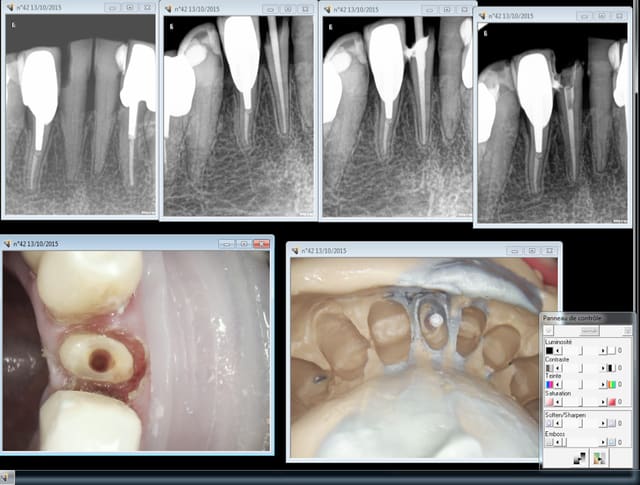

Heuh, si je peux me permettre, tigabi, on a ici une belle lyse osseuse horizontale (age ou parodontopatie) contre-indiquant un peu l'intraseptale!!!.

L'intracorticale assez basse ou tout betement la para-apicale sont dans ce cas particulier des indications de choix pour nos anesthésies.

Premier echec en distal de cette 33. Ca rentre mais difficilement du début à la fin, on sent pas la pénétration "par étages" je pense vu l'épaisseur du septum qu'une trans corticale aurait été plus judicieuse.

Par contre en mésial de 44 septum large pas de soucis.